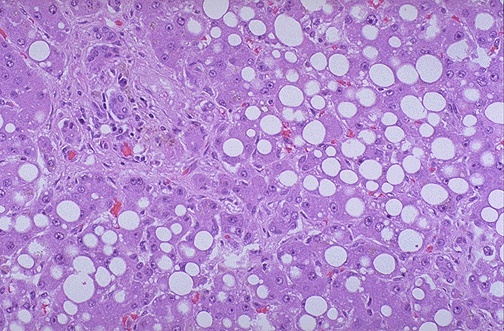

| Here are lipid vacuoles within hepatocytes in a case of macrovesicular steatosis (fatty change). The lipid accumulates when lipoprotein transport is disrupted and/or when fatty acids accumulate. Alcohol (ethanol), the most common cause, is a hepatotoxin that interferes with mitochondrial and microsomal function in hepatocytes, leading to an accumulation of lipid. |